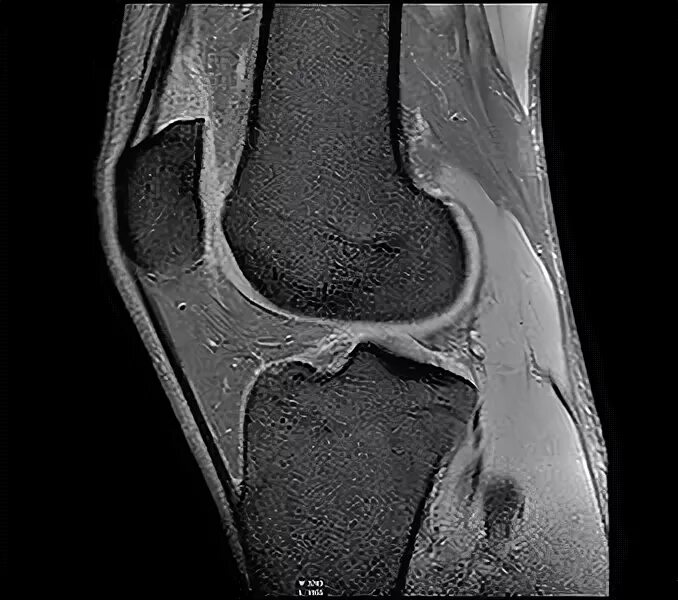

Мрт суставов кемерово